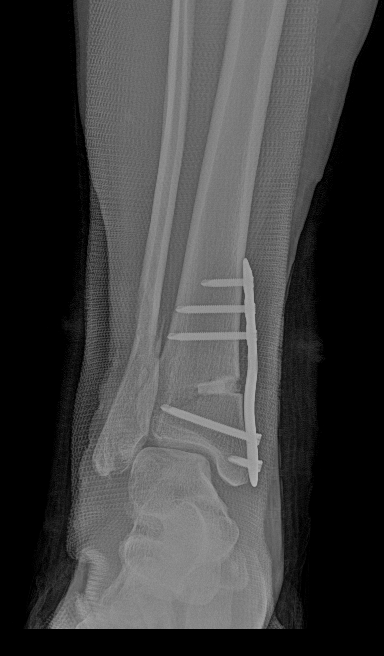

术后侧位X线

术后正位X线